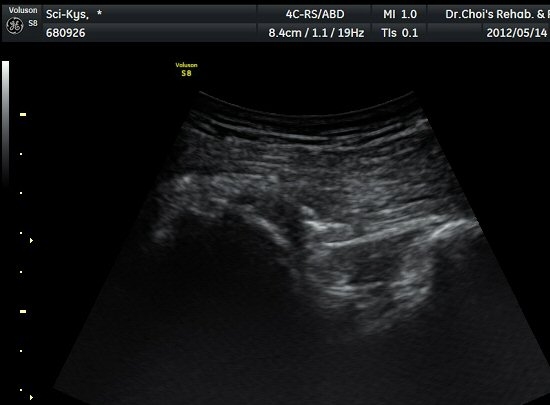

¾ûµ¢ÀÌ Á°ñ¿¡¼­ Á°ñ½Å°æ Ⱦ´Ü¸é°Ë»ç¿¡¼­ ´ëµÐ±Ù°ú quadratus femoris »çÀÌÀÇ ±Ù¸·

°æ°èºÎ¿¡¼­ Á°ñ½Å°æÀÌ °üÂûµÇ´Âµ¥ ³»Ãø Á°ñ°áÀý(ischial tuberosity) ÃøÀ¸·Î Ä¡¿ìÃÄ

ÀÖ´Â °ÍÀ¸·Î ÆÇ´ÜµÈ´Ù(±×¸² 1, 2, 3).